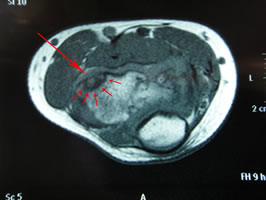

最後の画像(↓)はMRI T1での短軸(横向き)です。

やはり赤矢印の先に、離断性骨軟骨炎が描出されています。